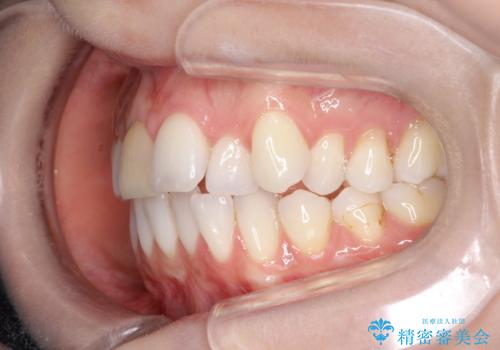

インビザラインによる非抜歯での八重歯の矯正

- 左上の八重歯と、上の歯のがたつきを主訴に来院されました。

上の奥歯を後方に移動させてスペースを作るのと、歯と歯の間をわずかに削り歯を並べる計画としました。

非常に強力的な患者様であったので、上下の正中も合わせ、ガタガタも改善することができました。